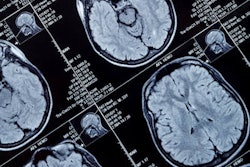

"The simplest answer is that we have better signal-to-noise ratios at 7 tesla that basically translate into higher-resolution images," Mukundan explained. "That allows us to resolve issues that are not easily seen at the lower field strengths. Tiny structural anomalies that are not well-discernible at lower field strengths, for example, in epilepsy and multiple sclerosis, have the advantage of 7 tesla."

More specifically, with 7-tesla MRI, BWH clinicians can see minute central veins within white-matter plaques of the brain's parenchyma. Gray-matter and cortical lesions are also identifiable at 7 tesla to evaluate these two conditions, he added.